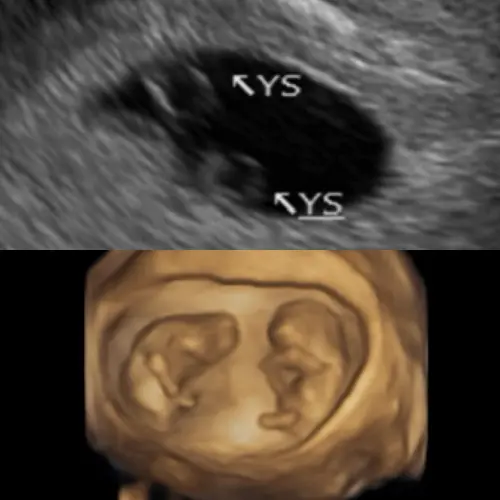

▲鄭家純分享孕肚超音波照,說明上圖為發現同卵雙胞胎的那一天,下圖是10週時所拍攝。(圖/鄭家純臉書) 鄭家純年初小產心碎淚崩 隔3個月喜懷雙胞胎

令鄭家純驚喜的是,5週產檢時發現是雙胞胎,6週即聽到心跳聲,讓她眼淚瞬間往下掉,8週時確認是雙羊膜,安心很多,不過歷經過小產的鄭家純說,「從驗到兩條線到10週,心理上很難受,會亂想這次留得住嗎?懷雙胞胎真的沒問題嗎?」